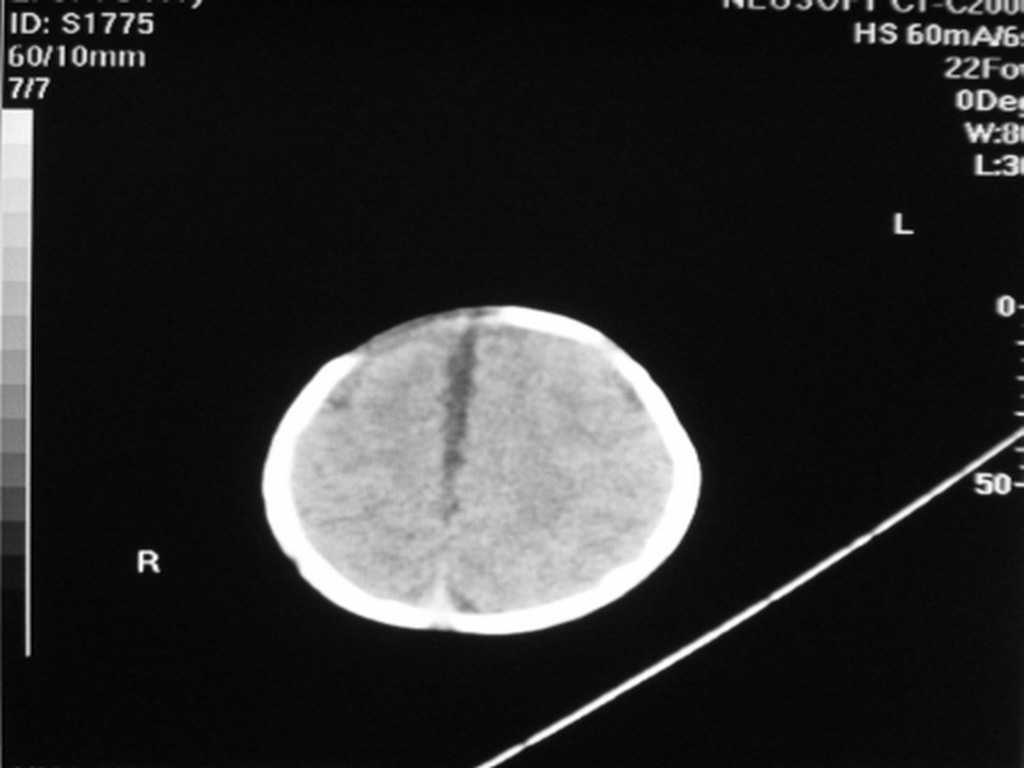

标题: PED1877:女,20余天,突发抽搐,双眼凝视。 [打印本页]

女,20余天,突发抽搐,双眼凝视。